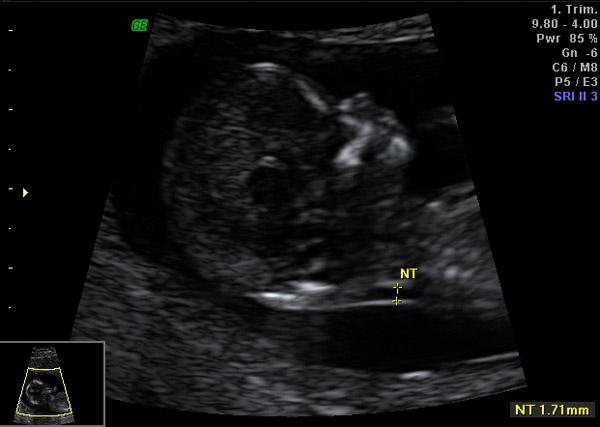

Jede Frau trägt ein gewisses Risiko ein Kind mit Down- Syndrom (Trisomie

21) oder schwerwiegenderen Chromosomenstörungen zu bekommen. Dieses

Risiko ist teilweise altersabhängig vorgegeben. Durch das Erst-Trimester-Screening

ist es möglich, eine individuelle Risikoanalyse für das Ungeborene

bereits zwischen der 12. und 14. Schwangerschaftswoche durchzuführen.

Dabei werden Enzyme des Mutterkuchens im mütterl. Blut bestimmt, die

Nackenfalte nach genauer Vorgabe sonographisch vermessen und andere

Risiken der Schwangerschaft erfasst. Diese Parameter werden in einem

Spezialprogramm verrechnet; als Ergebnis folgt eine individuelle Risikoanalyse

für die Wahrscheinlichkeit eines Down-Syndroms. Die Untersuchung ist

gefahrlos für Mutter und Föten und bringt eine ca. 90% verlässliches

Ergebnis. Die Methode ist seit über 10 Jahren etabliert und wird weltweit

angewandt. Leider wird diese Untersuchung von den gesetzlichen Krankenkassen

nicht bezahlt und ist somit eine Selbstzahlerleistung..